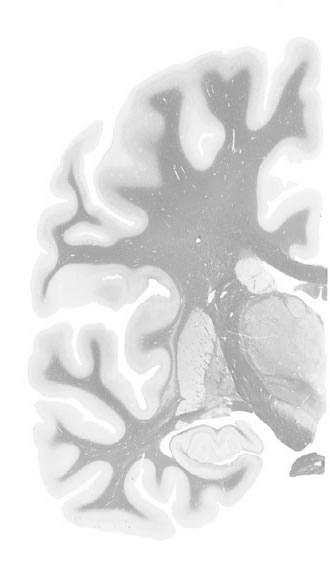

Frontal sections (Nissl) from the Atlas Brain: Gallery Slice Single

15,4 mm

Slice ID: r3-0824

Plate NR: ca 33-34

Position: 15,4 mm